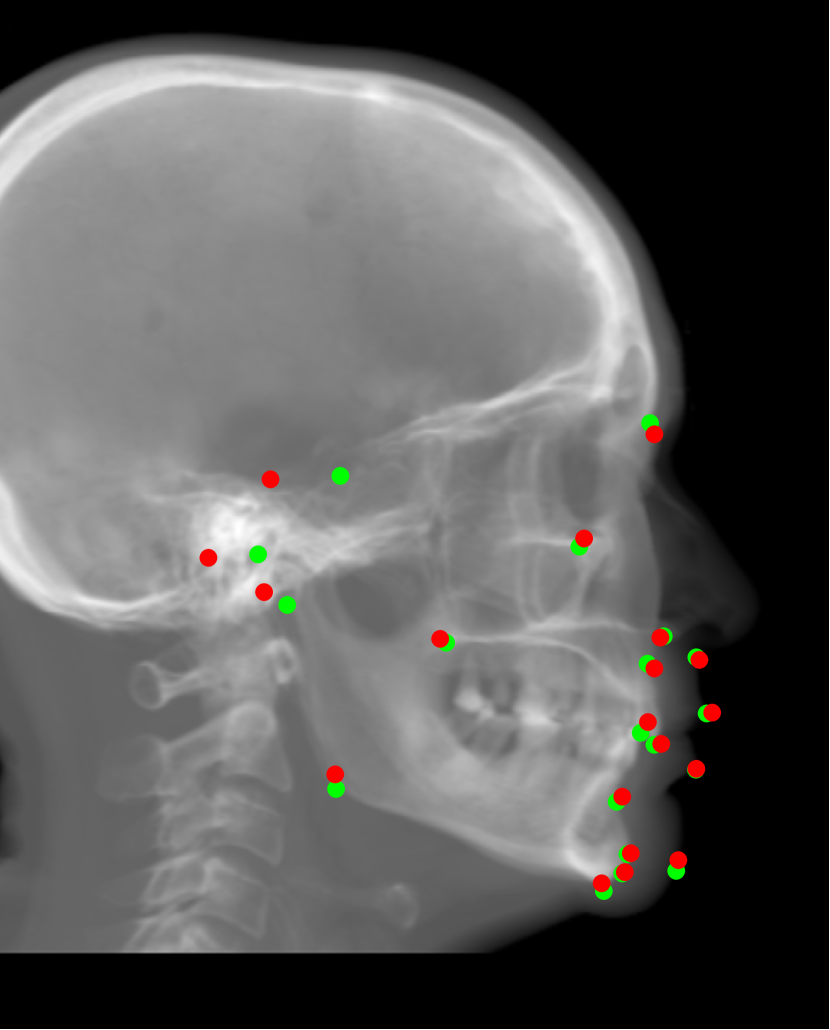

Fig. 16: Landmark detection on synthetic cephalograms. Cephalograms in the top row are obtained by different synthesis methods from 3D volumes for the first patient with pix2pixGAN for SR. The second row shows Type I synthetic cephalograms with different SR methods. The 3rd and bottom rows are Type I and Type II synthetic cephalograms respectively from three example patients with pix2pixGAN for SR. The green (reference) and blue labels are manual detection landmark positions in Type I and Type II synthetic cephalograms respectively, while the red labels are automated detection landmark positions in each cephalogram.

Our proposed landmark detection method is applied to detect landmarks in synthetic cephalograms. The results of three example patients are displayed in Fig. 16. Cephalograms in the top row are obtained by different synthesis methods from 3D volumes for the first patient with pix2pixGAN for SR. The second row shows Type I synthetic cephalograms with different SR methods. The 3rd and bottom rows are Type I and Type II synthetic cephalograms respectively from three example patients with pix2pixGAN for SR. The green and blue labels are manual detection landmark positions in Type I and Type II synthetic cephalograms respectively, while the red labels are automated detection landmark positions in each cephalogram. The green labels are used as the reference. The overall SDRs of the landmarks in different types of synthetic cephalograms on the test patients are displayed in Tab. 4. The last row SDRs are calculated from manual detection (blue) landmarks in Type II synthetic cephalograms w. r. t. reference landmarks, while others are from automatic detection (red) landmarks w. r. t. reference landmarks.

For RayCast in Fig. 16(a), many automatic detection landmarks exceed the 4 mm precision range such as the landmarks of anterior nasal spine, gonion, porion and articulare. According to Tab. 4, overall only 45.6% landmarks are detected within the 4 mm precision range by the automatic landmark detection algorithm. For MIP100 in Fig. 16(b), the landmarks of sella, porion, articulare have very large deviations from the reference landmarks. Overall, it achieves 47.4% 2 mm-SDR and 81.5% 4 mm-SDR. Figs. 16(c) and (g) are the cephalograms synthesized by our Type I synthesis with the original sigmoid transform and the modified sigmoid transform, respectively. These two synthetic cephalograms have subtle difference in the soft-tissue areas. As a result, the detected incision superius and lower lip positions exceed the 4 mm range in Fig. 16(c) while they are well detected within the 2 mm precision range in Fig. 16(g). This demonstrates the benefit of the modified sigmoid transform.

In Figs. 16(d)-(f), the landmark detection accuracies are very close to each other for the other 18 landmarks except for the sella landmark. The point-to-point errors are 9.77 mm, 4.57 mm, and 1.65 mm respectively in Figs. 16(d)-(f) for the sella. Tab. 4 indicates that overall 66.7% landmarks are detected within the 2 mm precision range for bicubic interpolation. For ESRGANRDB and ESRGANRRDB using ILR patches, the 2 mm-SDR rises to 70.2% and 71.9%, respectively. Nevertheless, pix2pixGAN achieves the best 2 mm-SDR 75.4% among different SR methods for Type I synthesis. Therefore, different SR methods have an influence on the landmark detection.

For Type I synthesis, two more cephalograms are displayed in Figs. 16(h) and (i). Overall, 93.0% automatic detection landmarks are overlapped with the reference landmarks within the precision range of 4 mm, with a few exceptions such as the sella landmark in (g), the porion in (h), and the incision inferius and subnasale landmarks in (i) beyond 4 mm. Particularly, 75.4% automatic detection landmarks are within the 2 mm clinical acceptable precision range. This indicates that the automatic landmark detection algorithms learned from real conventional cephalograms can be applied to our Type I synthetic cephalograms.

For Type II synthetic cephalograms in Figs. 16(j)-(l), all the manual detection (blue) landmarks are overlapped with the reference landmarks within the distance range of 4 mm, indicating that the landmark positions in the Type II synthetic cephalograms have no impactful position shift from those in Type I synthetic cephalograms. The majority (80.7%) of the automatic detection (red) landmarks are also overlapped with the reference landmarks within the 4 mm precision range. However, more automatic detection landmarks in Type II synthetic cephalograms are outside the 4 mm range than those in Type I synthetic cephalograms, for example, the anterior nasal spine landmark in (j), the orbitale landmark in (k), the incision inferius landmark in (l), the nasion landmarks in (k) and (l), and the gonion landmarks in (j)-(l). The 2 mm-SDR also decreases from 75.4% to 50.9%.